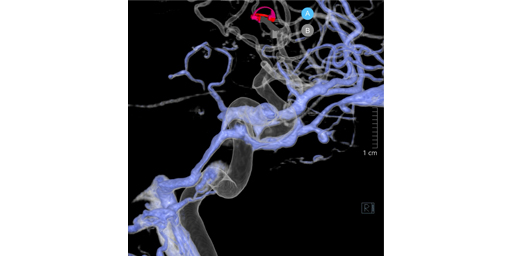

高分解能CBCTを用いた穿通枝描出テクニック